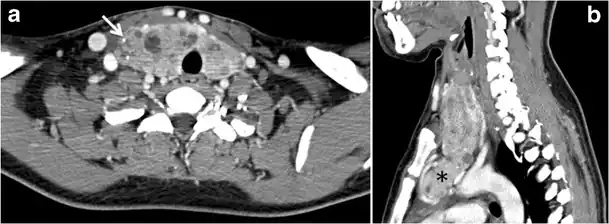

Fig. 13. A 27-year-old female patient known to have goiter. a, b Axial and sagittal enhanced CT scan images of the neck demonstrate a heterogeneously enhancing, enlarged thyroid gland with scattered calcifications (white arrow), cystic changes, and substantial retro-sternal extension (black asterisks). No lymphadenopathy or substantial airway narrowing.[1]

-